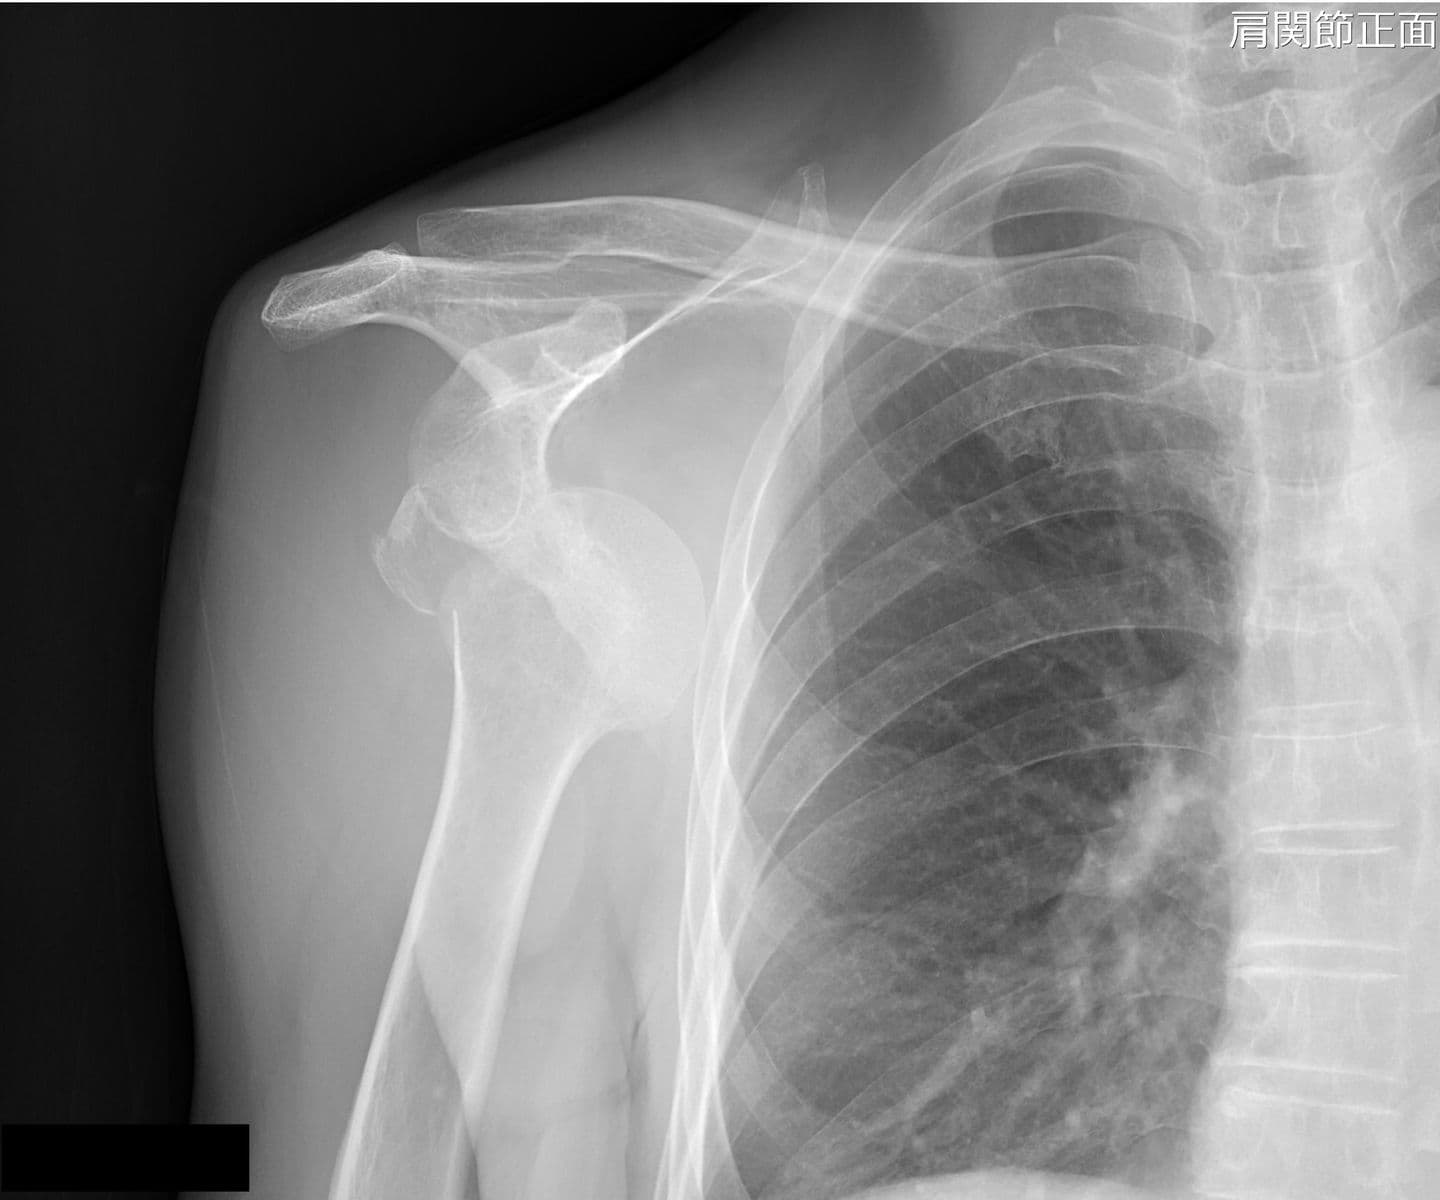

整形外科では、椎間板ヘルニアなどによる神経障害の痛みを軽減させる神経根ブロックなどの治療を行っています。また、脊髄腔や様々な関節腔(肩関節、股関節、手関節など)に造影剤を注入し、関節腔の形態を調べます。

寝台が広いため、骨折や関節脱臼をX線透視下で確認しながらの整復を行っています。

また、断層撮影が可能となっており、一度の撮影で骨の重なりを避けた高精細の画像を得ることができます。